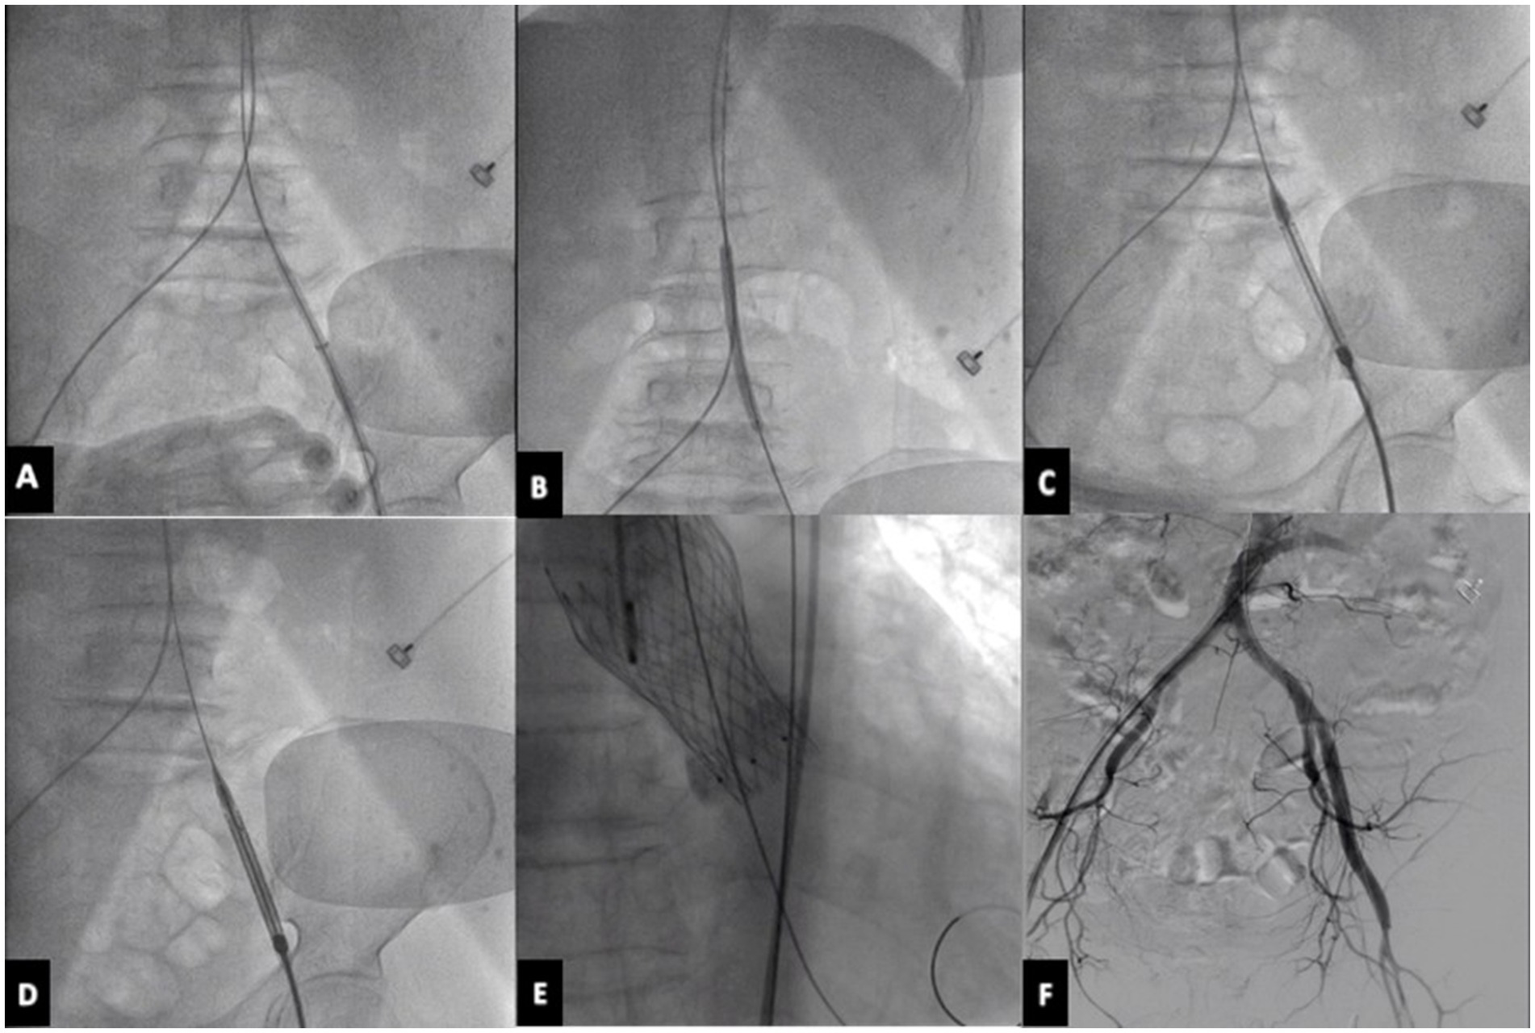

The left or right femoral artery was used as the main approach, and the femoral artery was punctured with a 16F expandable arterial sheath tube and embedded 2 staplers in advance (Perclose Proglide). A 6 mm*10 cm or 6*8 cm balloon is used in the sheath to dilate the femoral artery stenosis and equally increase the vascular diameter. Intrathecal dilation can rely on the sheath to indirectly compress the blood vessels, so that the blood vessels are more evenly stressed, and the balloon dilation is safer and easier to obtain a larger lumen, reducing the risk of vascular dissection, vascular rupture, and vascular occlusion. Next, try to push the empty delivery system without a valve through, and then place the VENUS-A aortic valve. Angiography is performed to observe the position of the valve, whether the valve is released well, whether there is an obvious paravalvular fistula, and whether there is aortic valve regurgitation. Then the interventional valve delivery system is slowly withdrawn, meanwhile pushing the contrast agent, we should monitor this whole withdrawal procedure carefully under fluoroscopy. Finally, the iliofemoral artery is essential to be examined by angiography. If there is damage, the iliac or femoral artery should be quickly implanted with a stent along the guide wire (Figure 1).

Figure 1

TAVR procedure. (A) Puncture the femoral artery with 16F expandable arterial sheath tube. (B) Use a balloon in the sheath to dilate the femoral artery stenosis. (C) Try to push the empty delivery system without a valve through. (D) Load and deliver the VENUS-A valve using the delivery system. (E) Release the prosthetic aortic valve. (F) Perform angiography on the iliofemoral artery to assess for any potential damage. TAVR, transcatheter aortic valve replacement.